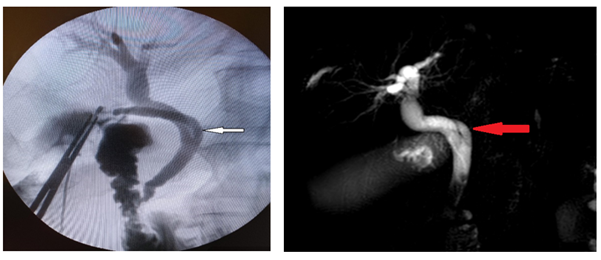

Ultrasound of the abdomen and pelvis revealed a dilated gallbladder with a thicker wall and with stones. The common bile duct (CBD) measured 15 mm in diameter, and stones were visible within it. Furthermore, the ultrasonography revealed the dilatation of the intrahepatic bile ducts. MRCP was conducted using 1.5 T MRI (Ingenia; Philips Healthcare, Best, the Netherlands) in the coronal, axial, and sagittal planes in accordance with standard protocol. T2-weighted sequences in multi planar reconstruction were used for the evaluation. Respiratory-triggered T2 SPAIR axial and T2 coronal sequences with slice thickness of 5 mm, comprising the liver and region, were acquired. The MRCP revealed a gallbladder with 3 small stones and a 16 mm-diameter common bile duct (CBD) with four stones visible inside. Furthermore, coronal oblique 3D MRCP showed posterior spiral course of cystic duct with medial insertion with CHD (Figure 1)

Figure 1: Coronal oblique 3D MR cholangiopancreatography (A and B) and T2w-SPAIR sequence in axial plane (C) show posterior spiral course of cystic duct (red arrow) with medial insertion with CHD.

Before the end of the operation, intraoperative cholangiogram was performed through the cystic duct, which showed in the affirmative spiral course of cystic duct with medial insertion with CHD, intact CBD, CHD, as well as right and left hepatic ducts without stones (Figure 2).

Figure 2: Intraoperative cholangiogram shows spiral course of cystic duct (white arrow) with medial insertion with CHD.